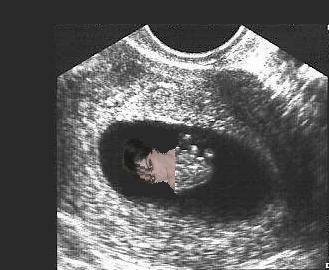

We had a little scare on Friday and I was given an early ultrasound. Fortunately, everything looked good. Baby measured just right for it's age (about 8wks) at 1.5cm and the little heart was beating along at a steady 145bpm (also very good). Everything else looked good as well. I thought I would include a picture for anyone interested.

baby2.jpg

baby2.jpg [ 19.12 KiB | Viewed 5006 times ]